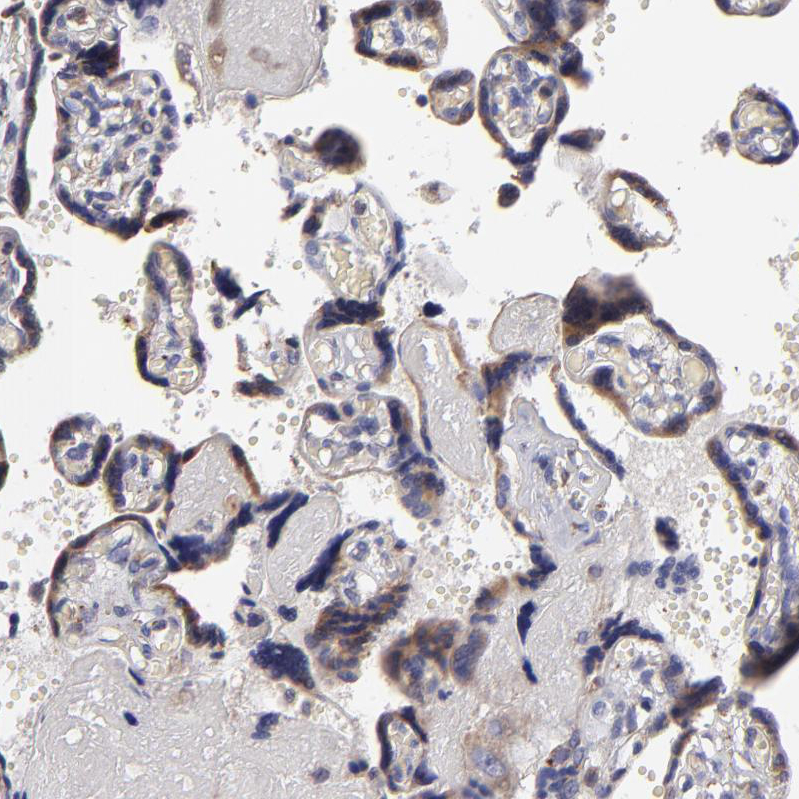

Immunohistochemistry analysis in human thyroid gland and skeletal muscle tissues using HPA002242 antibody. Corresponding CALR RNA-seq data are presented for the same tissues.